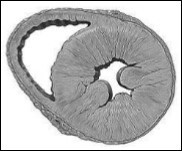

HFpEF, LV cavity typically has a normal volume and the walls are hypertrophic. See Figure 2. Histological examination shows the deposition of collagen and cardiomyocytes larger, stiffer than in HFrEF4. Despite the different cardiac structure and function, HFrEF and HFpEF hemodynamic patterns share similarities as well as differences. The clinical symptoms, renal dysfunction, neurohormonal activation, response to exercise and clinical findings may overlap10 However, increased ventricular and vascular stiffness can play a greater role than a real volume overload, in HFpEF compared with HFrEF. Thus, these two forms of IC are two well differentiated entities, with different pathophysiology and therapeutic approaches accordingly.

Figure 2.Model of concentric left ventricular hypertrophy, common in HFpEF.

Model of concentric left ventricular hypertrophy, common in HFpEF.